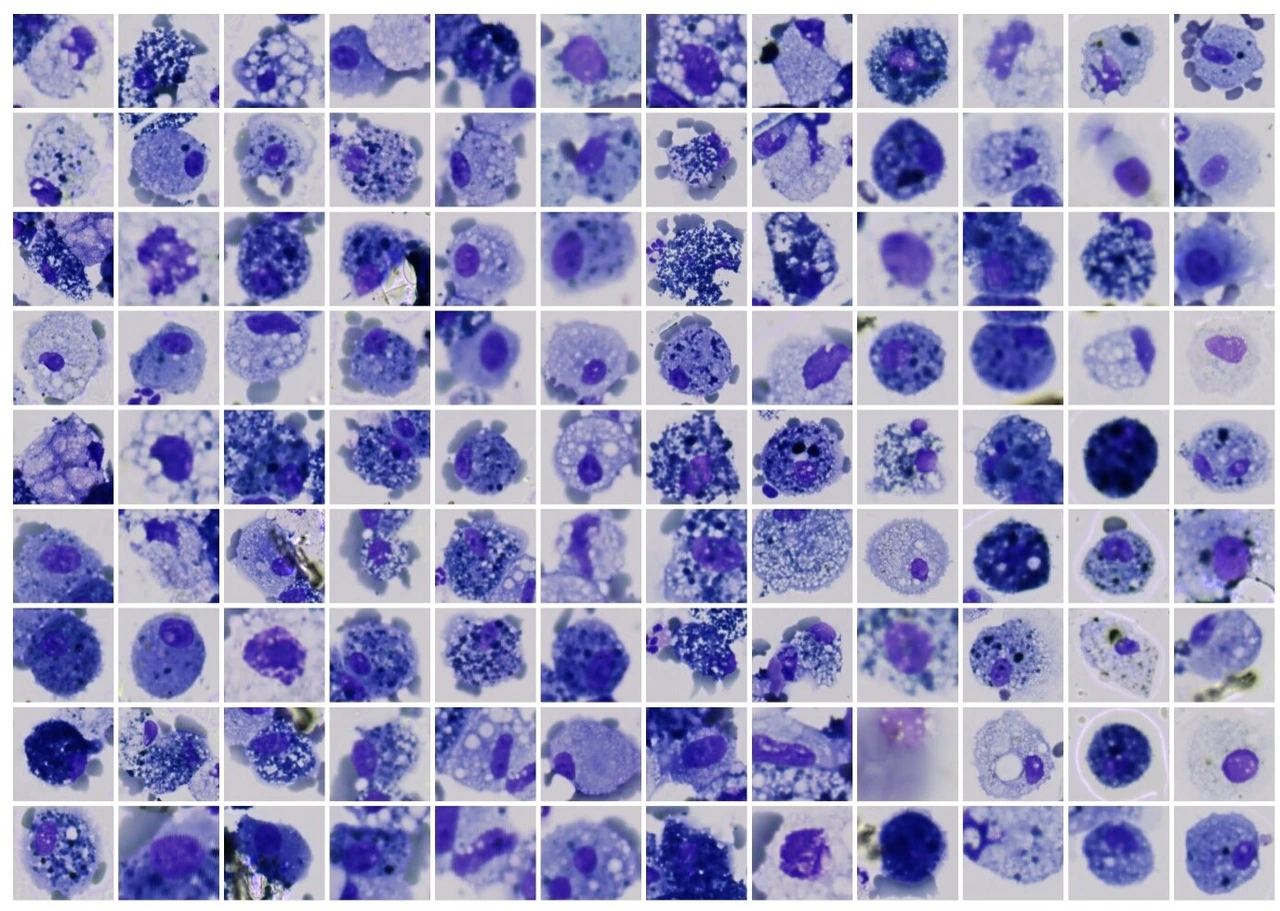

Many environmentally triggered lung diseases are still considered incurable. We explore the immunological mechanisms underlying chronic lung diseases such as COPD, lung fibrosis, asthma, lung cancer and the complications following lung transplantation. We want to translate our findings into preventative and therapeutic approaches for patients.

Many environmentally triggered lung diseases are still considered incurable. We at the Institute of Lung Health and Immunity (LHI) explore the immunological mechanisms underlying chronic lung diseases such as COPD, lung fibrosis, asthma, lung cancer and the complications following lung transplantation. We want to translate our findings into preventative and therapeutic approaches for patients.